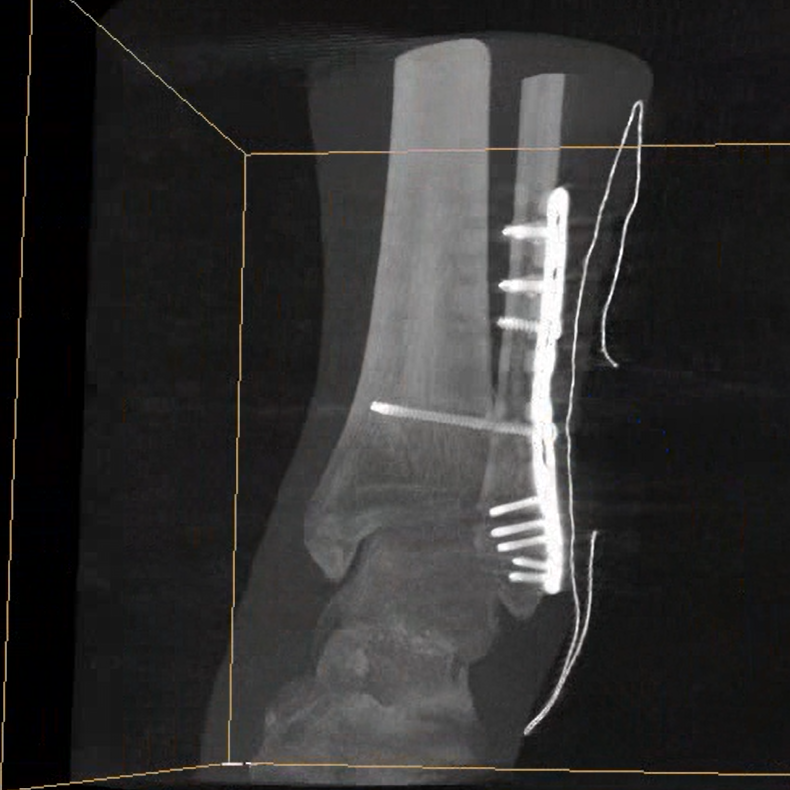

術(shù)中三維成像和橫斷面圖像提供多角度的手術(shù)診斷信息,輔助醫(yī)生進行術(shù)中評估判斷,諸如骨折復位情況和內(nèi)植入螺釘?shù)某叽绾臀恢茫o助手術(shù)更好地完成。